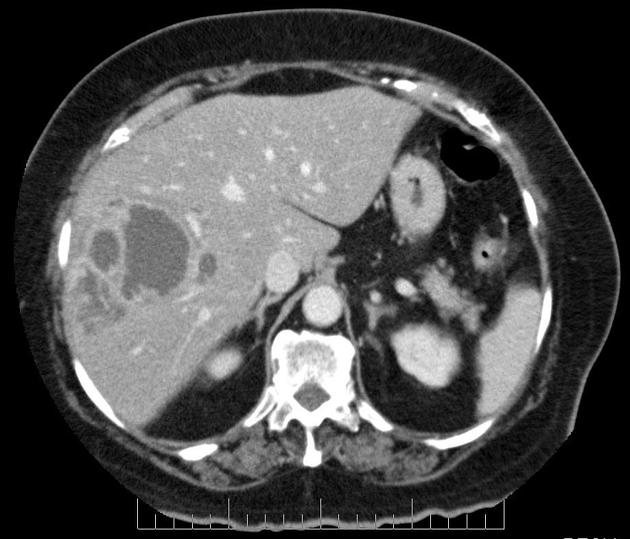

A 40-year-old man presents to the office with complaints of epigastric discomfort for the past 6 months. He adds that the discomfort is not that bothersome as it does not interfere with his daily activities. He does not have any other complaints at the moment. The past medical history is insignificant. He is a non-smoker and does not consume alcohol. He recently came back from a trip to South America where he visited a relative who owned a sheep farm. On physical examination, he has a poorly palpable epigastric non-tender mass with no organomegaly. The hepatitis B and C serology are negative. The liver CT scan and MRI are shown. What is the most likely diagnosis?